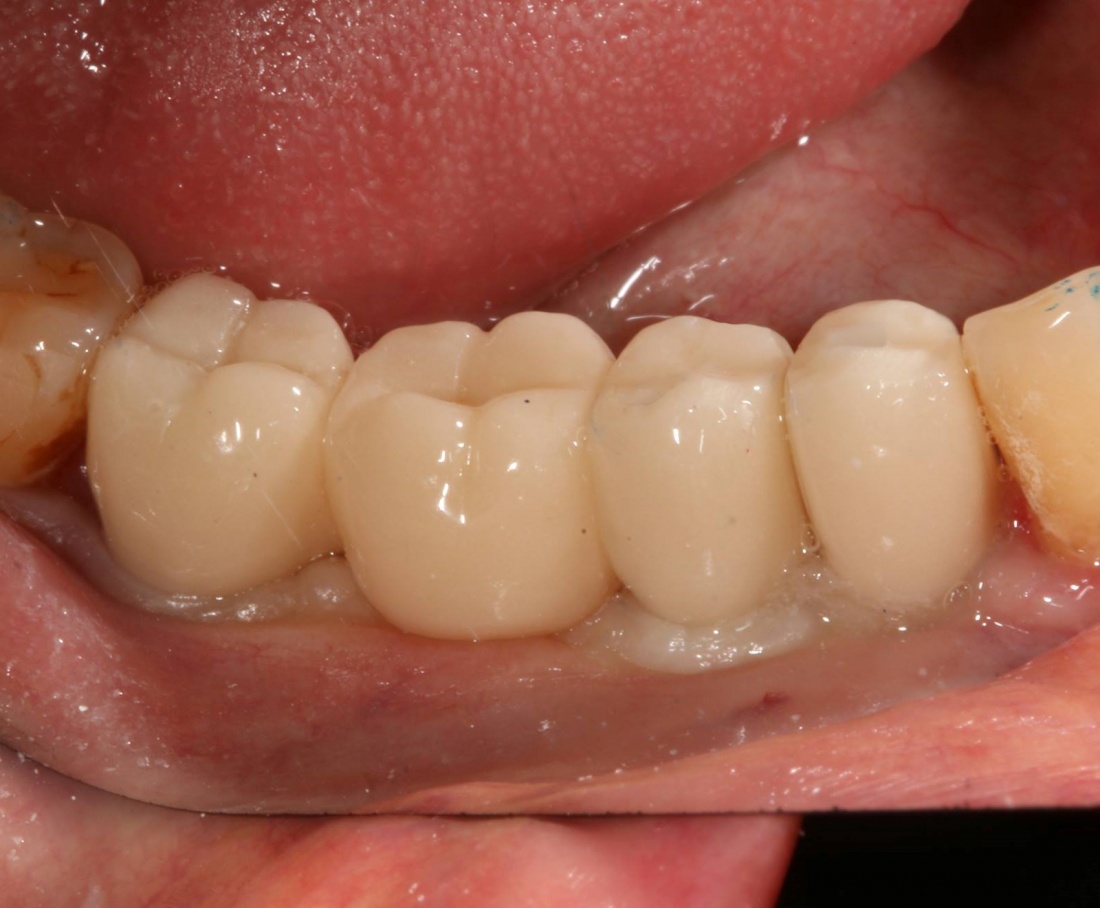

Рекомендации по установке имплантов. Для всех. Часть V.